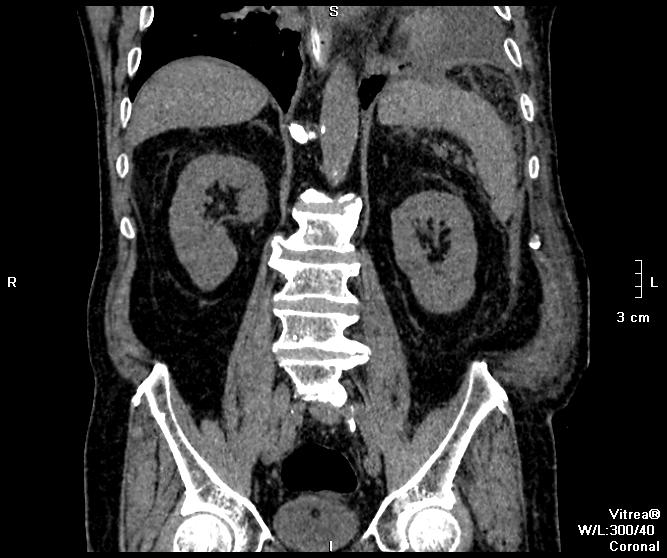

Пациент поступил ко мне через 6 дней после ушивания перфоративной язвы ДПК. УЗИ-сты увидели инфильтративно-жидкостные изменения в зоне оперативного вмешательства, пузырьки газа. Но смутило найденное образование в пространстве между правой долей печени и паранефрием. цель исследования - дифференцировать найденное между инфильтрацией и жидкостным скоплением.

Пациента готовили в течение 2 часов, перорально разведенный урографинчик дробно, и пол станканчика перед исследованием (это важно). Болюс в артериальную и венозную фазы.

мы имеем - задренированное околопеченочное пространство, жидкость в подпеченочном, левом поддиафрагмальном пространстве и по контурам селезенки (серозная), к передне-наружному контуру левой доли печени прилежит ограниченное жидкостное скопление

-ничего криминального между висцеральной поверхностью печени и правой почкой (паранефрий как им угодно) не вижу

- меня смущает не типичный вид артериальной фазы, и уж тем более венозной

Усиление коркового вещества слабое, задержка начала нефрографической фазы. диаметр почечным артерий около 5 мм, почечных вен -- 10мм. на 60 секунде отсутствует должное конрастирование вен, без признаков патологического сброса

В первом случае дополнительно, как мне кажется, в обеих плевральных полостях есть жидкость, средостение смещено влево, наличие осумкованной жидкости в слева паракостально. По нижнему полюсу левой почки киста.

Случай 1. Атеросклероз сосудов, запаздывание фаз секунд на 20-25. Получили раннюю артериальную фазу (посмотрите контрастирование камер сердца). И вместо портальной - нечто между поздней артериальной и портальной. Стоило, как мне кажется, сделать 85-90 сек, тогда бы попали в порталку.

По поводу жидкостей в брюшной полости (инфильтраты? где? Виталий показывает скопление жидкости у левой венечной связки) - нормальное послеоперационное их распределение, результат самой операции - т.е. лизированная кровь, ничего криминального, в соответствии с анатомией связок (в том числе и левой венечной, селезеночно-ободочной, желудочно-диафрагмальной)), обычная п/о реакция клетчатки. Абсцессов нет.